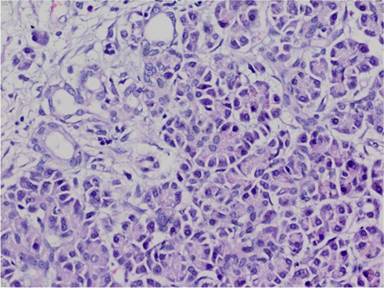

Microscopic examination revealed aberrant pancreatic tissue consisting of acini, intra and interlobular ducts and some chromogranin A and few synaptophysin expressing islet cells (Figures 2, 3, and 4). No direct connection with the gallbladder lumen was observed. A chronic inflammatory reaction with some eosinophils was also seen at subepithelial areas.

Figure 3. Ductal and acinic structures (H&E x400). |